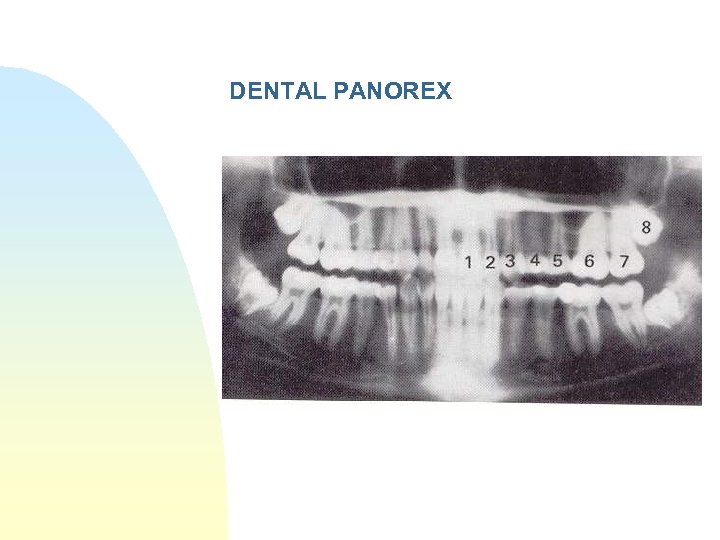

Investigations n n Tongue Depressor test plain films esp panorex usually adequate

TAKE HOME POINTS n Waters view overall most useful view mid face n Panorex most useful view for mandible n CTScan most useful modality for Orbits and Maxilla